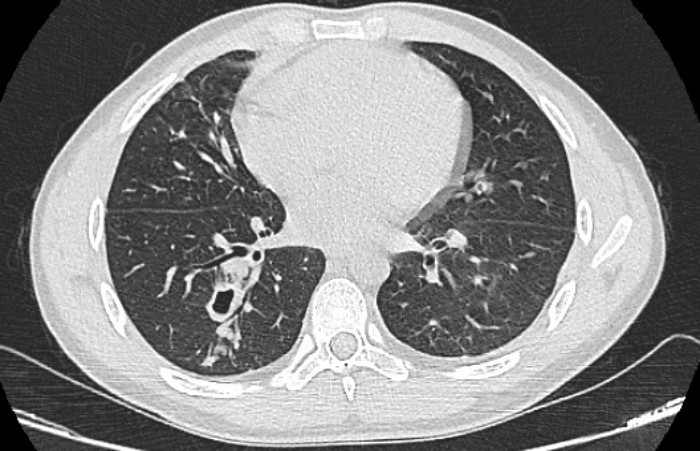

Hình ảnh phim chụp cắt lớp phổi của bệnh nhân sán lá phổi. (Ảnh: BVCC)